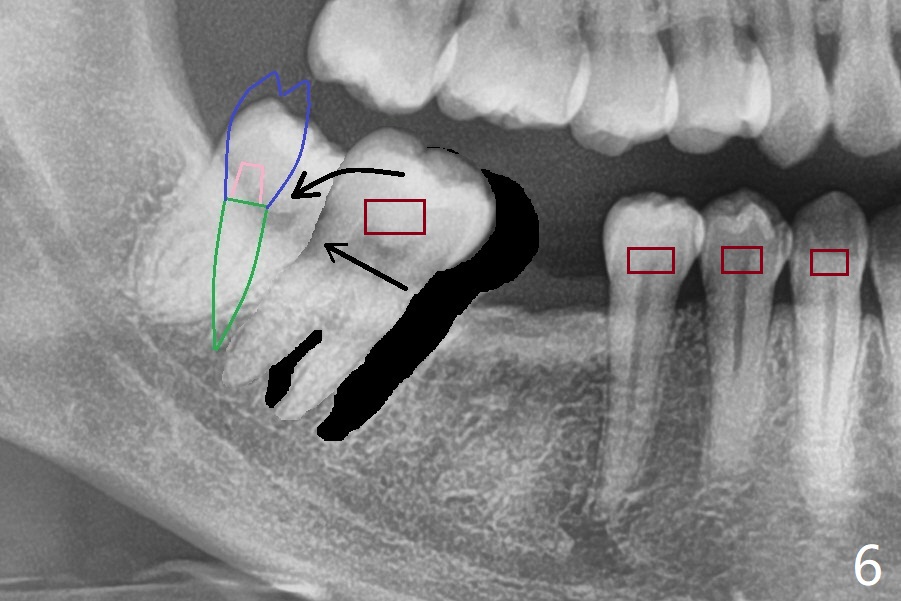

27岁女,小的时候在国内做过牙齿矫正,留下不好印象,不愿意再次矫正。她缺失右下6;7,8明显近中移位(图一,二)。左下7近中颊侧牙尖位于上6,7之间(图三:^),理论上,右下7必须远中移位到8牙位一半(图四)。经过反复讨论(包括前移7,8),病人同意拔除8,做右下后牙区矫正。为了有效7远中移位,拔除8后即刻种植(图五:绿色),植骨(红圆圈),覆盖PRF膜(紫色线)。一旦植牙整合,制作临时牙冠(图六:蓝色;并且提高咬合,这样7有垂直空间后移(直箭头)旋转(弯箭头)),永久性粘固,可能在7,8之间使用power chain,起牵拉作用,棕色方块代表矫正器。一旦6空间扩大,植牙。整合后也可以作为支抗,继续将7远中推移。一定时光,取出智齿植体,完成暂时性支抗作用。